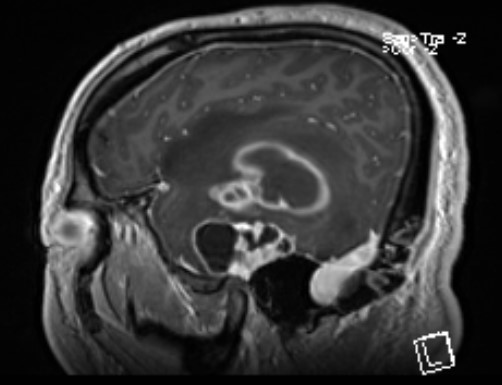

患者,男性,59岁,头痛伴四肢无力一周入院

头部MR提示:右颞叶,岛叶及基底节区巨大占位,胶质母细胞瘤可能性大

矢状位